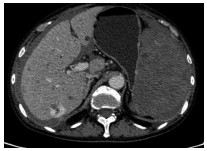

A preliminary study on percutaneous transhepatic drainage combined with sequential percutaneous nephroscopy in treatment of refractory liver abscess

Changhu DUAN, Xiaochen LIU, Jianlong DING, Jianfeng DUAN, Xirong ZHAO, Fan YANG, Ling WU, Lifei ZHAO, Sheng TAI

2021, 37(11): 2622-2625. DOI: 10.3969/j.issn.1001-5256.2021.11.026

Abstract(1082) HTML (221) PDF (2925KB)(64)

Abstract:

Objective  To investigate the clinical effect of percutaneous transhepatic drainage combined with sequential percutaneous nephroscopy for necrosectomy and drainage in the treatment of refractory liver abscess after transcatheter arterial embolization (TACE).  Methods  A retrospective analysis was performed for three patients with refractory liver abscess after TACE in The Affiliated 3201 Hospital of Xi'an Jiaotong University School of Medicine from January 2018 to December 2020, and among the three patients, one had the formation of liver abscess after TACE for hepatic metastases after pancreaticoduodenectomy, one had liver abscess after repeated TACE for massive hepatocellular carcinoma, and one had secondary liver abscess after TACE for traumatic hepatic rupture. All three patients received percutaneous transhepatic drainage and sequential percutaneous nephroscopy for the treatment of refractory liver abscess, and their specific treatment process was summarized.  Results  All three patients were diagnosed with refractory liver abscess based on CT, routine blood test, procalcitonin, blood culture, and clinical manifestation. Percutaneous transhepatic catheterization under the guidance of conventional ultrasonography or CT and effective antibiotics had an unsatisfactory therapeutic effect, and after sequential percutaneous nephroscopy was performed for necrosectomy and drainage, liver abscess was cured and the patients had good prognosis.  Conclusion  For refractory liver abscess after TACE, when routine puncture treatment has an unsatisfactory therapeutic effect or a patient cannot tolerate surgical operation, percutaneous transhepatic drainage combined with sequential percutaneous nephroscopy is safe and effective in the treatment of refractory liver abscess.